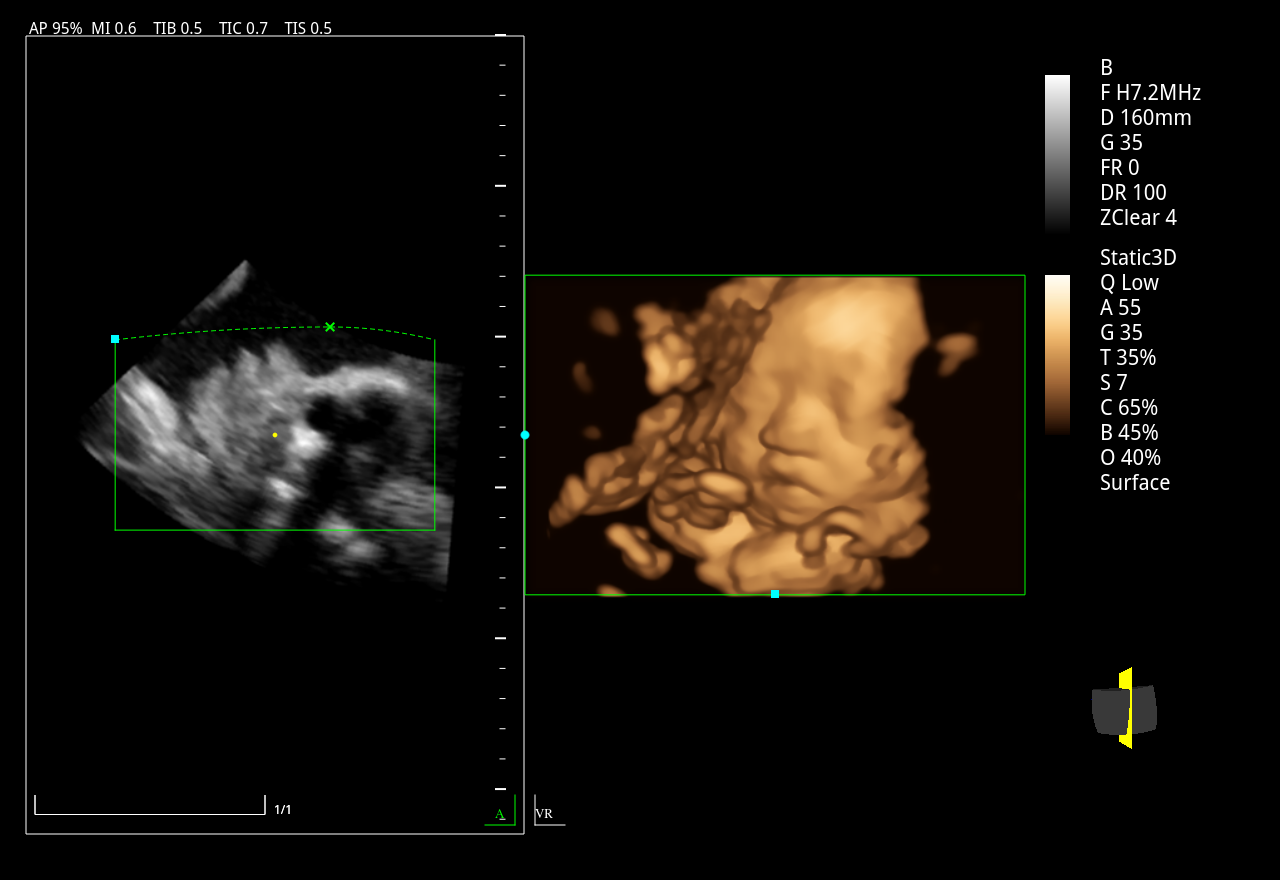

Abdomen, Obstetricia y Ginecología

Volumétrico 4D

3D / 4D (ZLive, Silhouette)

Imágenes clínicas extraordinarias